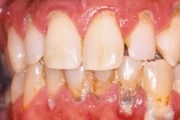

- puudulik suuhügieen (5)

- igemepealne hambakivi (5)

- igemealune hambakivi (4)

- igemepiir on taandunud (3)

- igemed veritsevad (19)

- igemed punetavad (21)